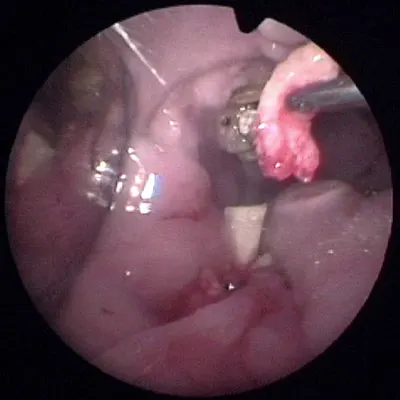

Definitive DiagnosisComplete evaluation of dental disease in rabbits requires at minimum full oral examination performed under anesthesia and skull radiographs. Anesthetic protocols for rabbits are described elsewhere. Oral examination is greatly facilitated by endoscopy. Proper instrumentation is required for thorough evaluation (Table 1, Figure 1).

Figure 1

Featured Image